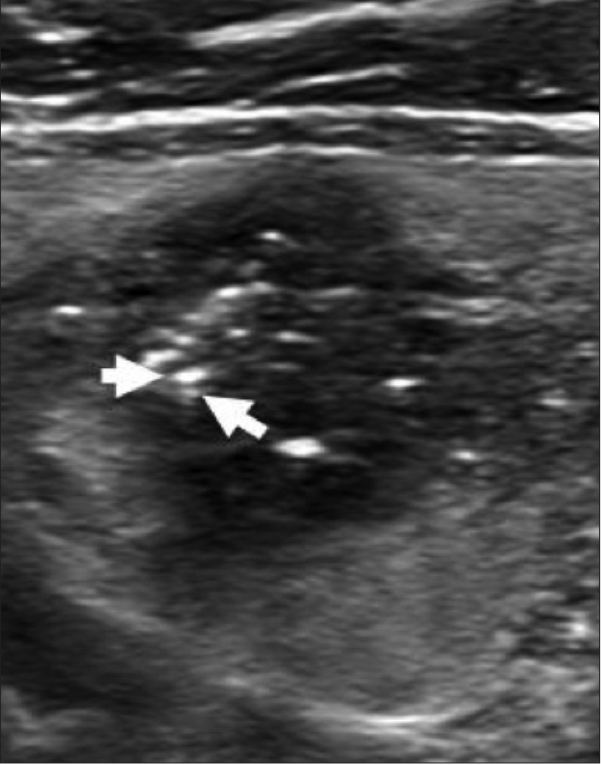

体检发现甲状腺结节伴有钙化,穿刺确诊为“甲状腺乳头状癌”,医生却建议“观察”——这看似矛盾的决策让23岁的你不知所措。近期,门诊遇到一位年轻甲状腺癌患者小美,大学刚刚毕业工作第一年体检就发现甲状腺4.7mm结节,伴有钙化,外院活检明确诊断为经典型乳头状癌。对此,医生建议观察,焦虑失眠了3天后,患者决定门诊寻求中西医治疗。

你的报告中提到了“伴有钙化”,这是一个需要仔细分析的特征。钙化分为不同类型,其风险程度也不同:

| 微小钙化 | 砂砾状/针尖样 | ★★★★★ | 需要警惕,进一步评估 |

高频超声(>10MHz探头)

弹性成像(评估硬度分级)

CT增强(观察钙化立体分布)